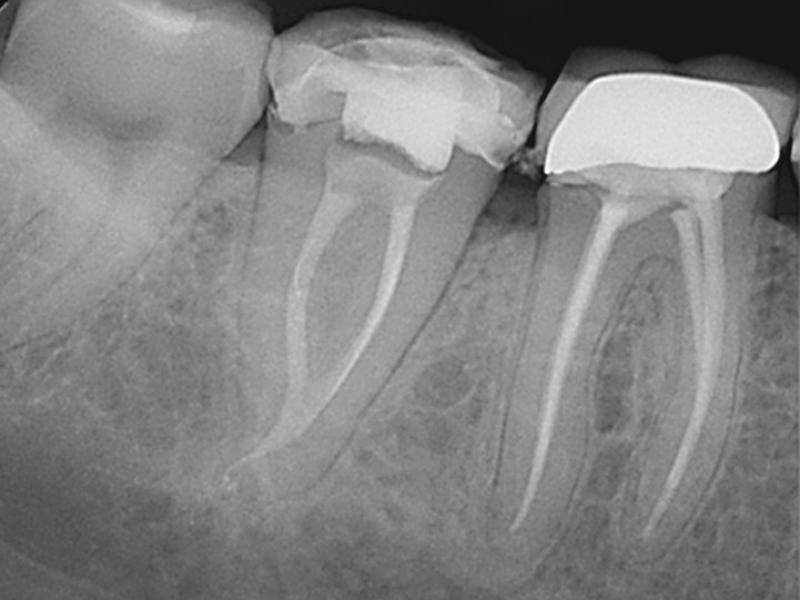

C-Shaped Canal

Pre-Op

Post-Op